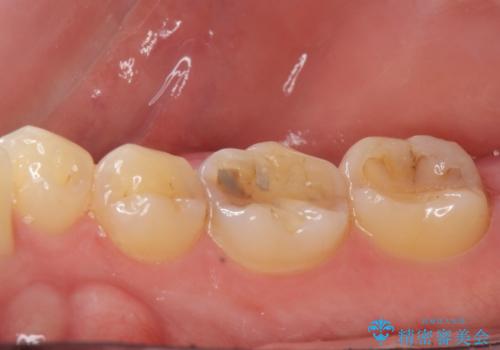

セラミックインレー。

- セラミック治療希望の患者様です。

古い樹脂の材料をとりe-maxの詰め物で治療を行いました。

- e-maxインレー 7.7万×2費用は治療当時の料金となります